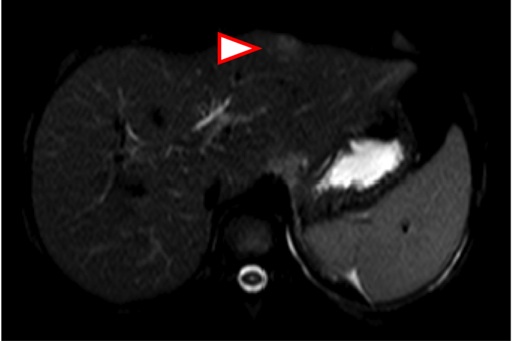

da possibili localizzazioni linfomatose. Figura 2. L�RMN

mostra numerose lesioni solide epatospleniche con intensa

ipervascolarizzazione in fase arteriosa a cercine di natura

infettiva. Figura 3. L�ecografia

lui, ma non ha linfonodi palpabili. Finalmente esegue la RMN (Figura 2) �lesioni solide epatospleniche con

intensa ipervascolarizzazione in fase arteriosa a cercine. Di natura

infiammatoria-infettiva

(lesioni granulomatose?)�